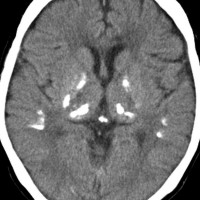

全脳照射後の脳内石灰化(幼児例)

20年以上前のことですが,髄芽腫の1歳6ヶ月の子どもに25グレイの全脳照射をしました。これは15年後のCTです。

脳の萎縮は目立ちません。認知機能は低いのですが支援を受けて学校へ行けています。下垂体機能は低下して成長ホルモンなどの補充をして普通に暮らせています。

CTで,両側の大脳基底核(被殻と淡蒼球)と視床後部に石灰化がみられます。乳幼児期に放射線治療を受けた子どもに見られるものです。